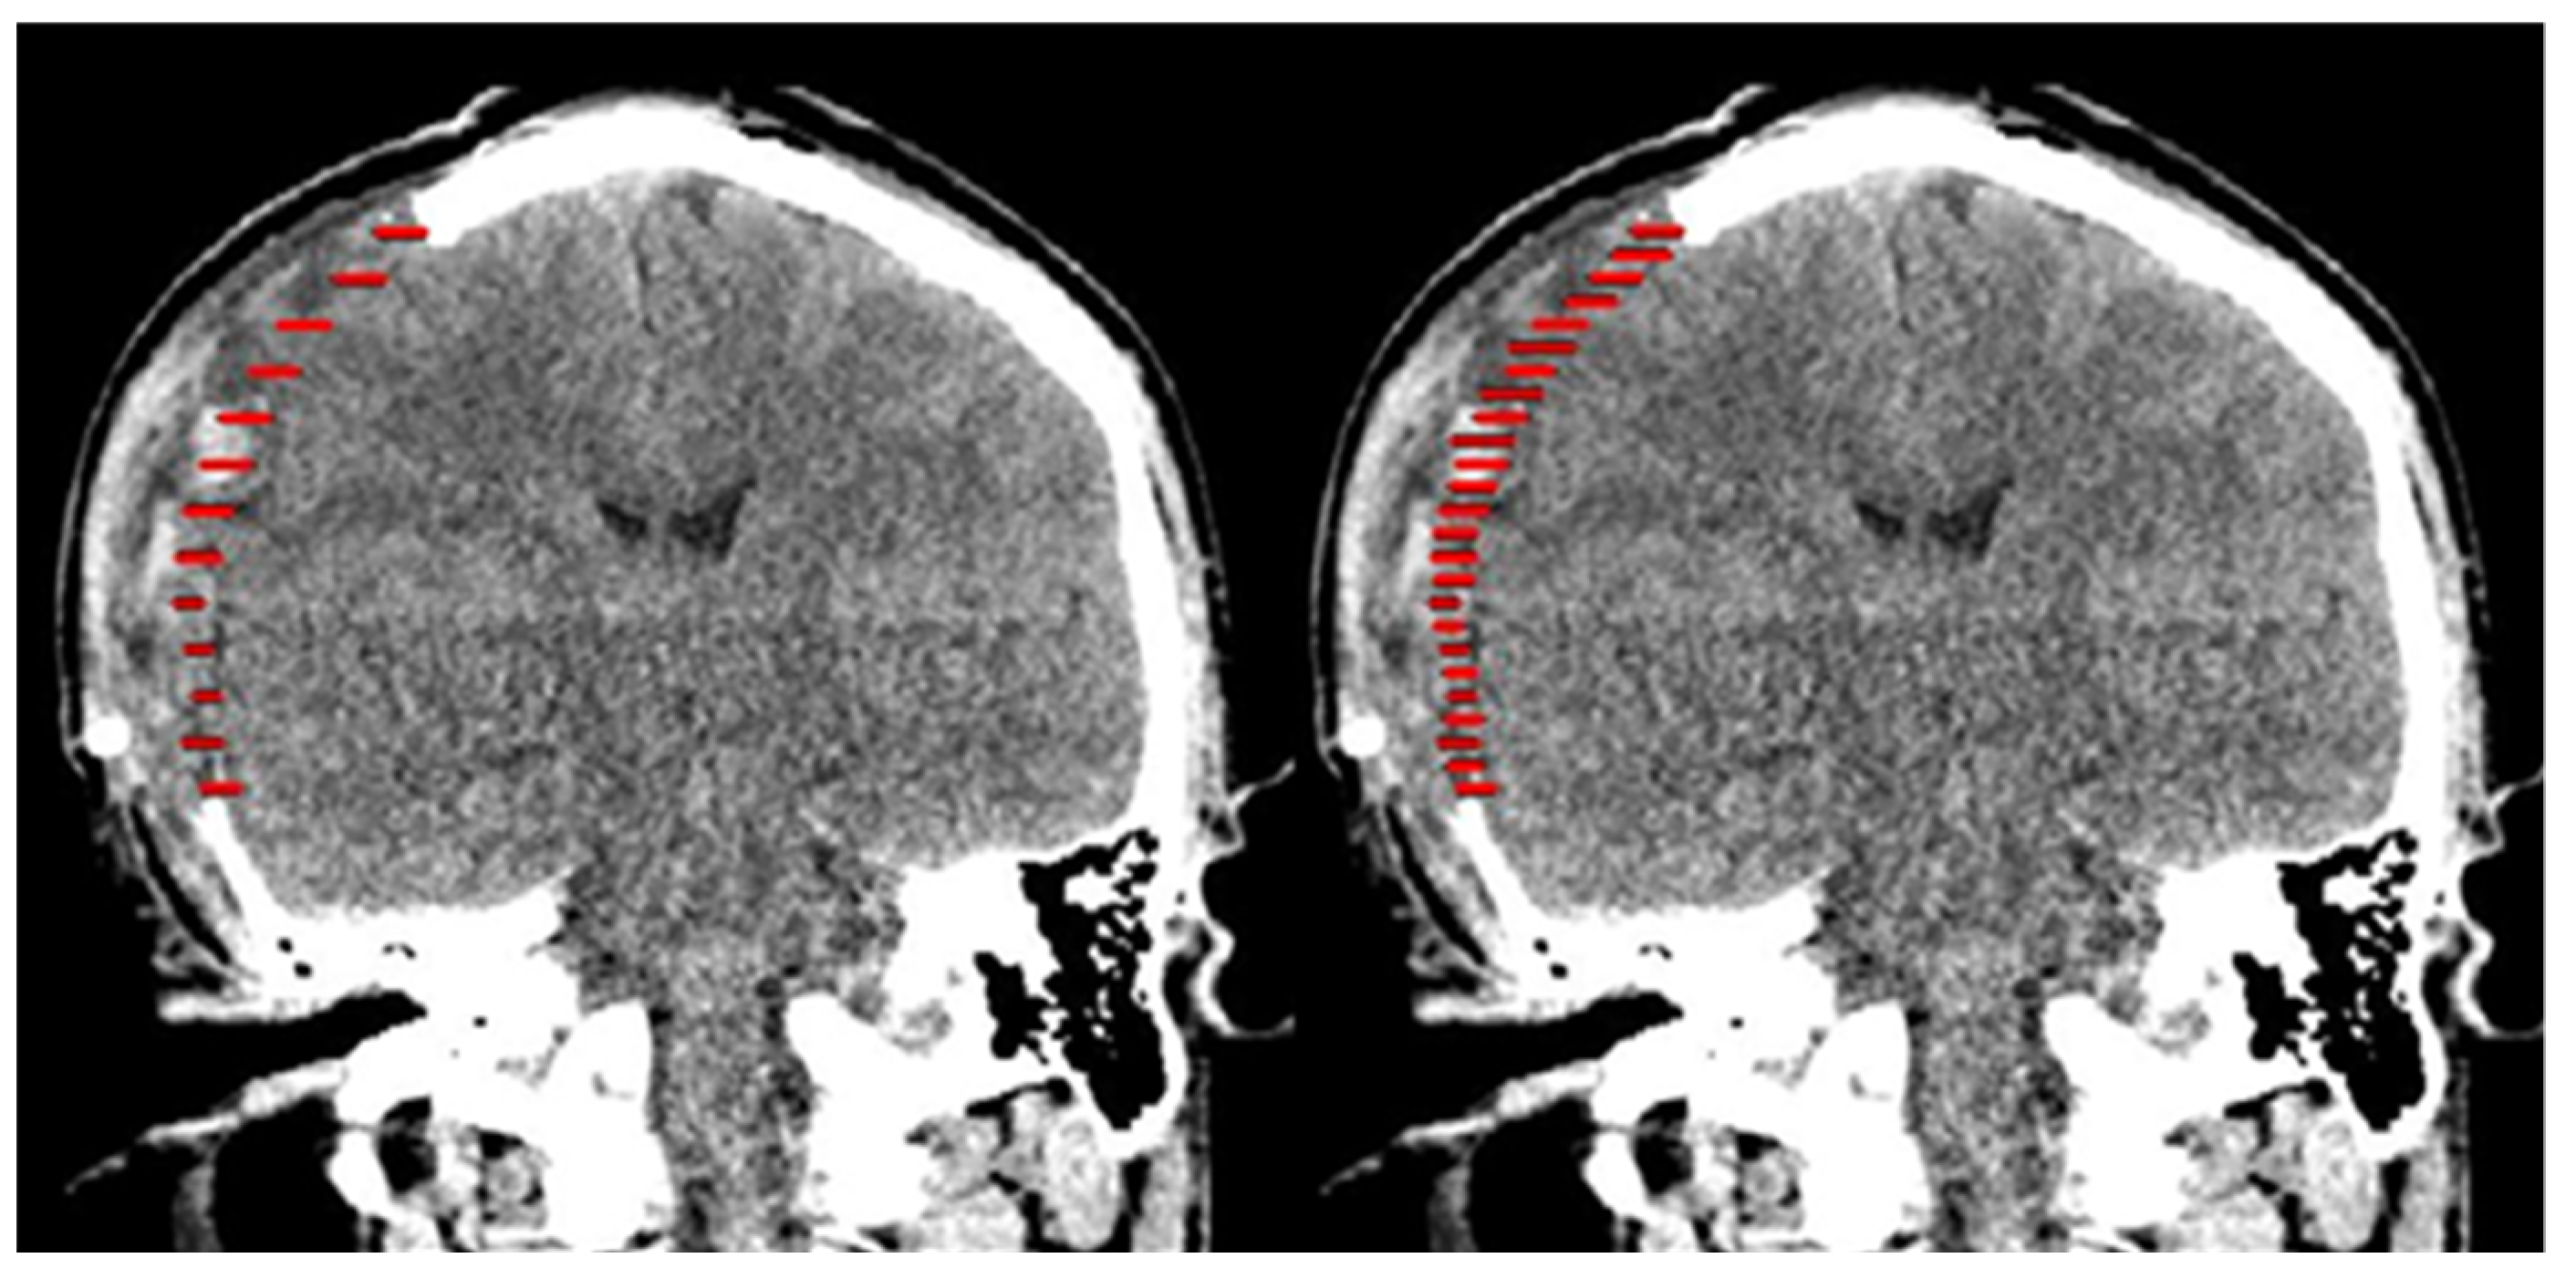

Alternatively, another method of selecting every fifth slice for interpolation was tested, as shown in Figure 7.

Figure 7.

Lines drawn on every tenth axial slice (left) and every fifth slice (right) on the coronal slice of CT data.

When every fifth slice interpolation method was performed, the slices involved were 91, 96, 101, 106, 111, 116, 121, 126, 131, 136, 141, 146, 151, 156, 161, 166, 171, 176, 181, 186, 191, 196, 201, 206, 211, 216, and 221. The total number of slices was 27. The result of the patient-specific cranial implant using the shape-based interpolation method on every tenth slice and fifth slice were saved in STL format and exported to STL format, as shown in Figure 8.